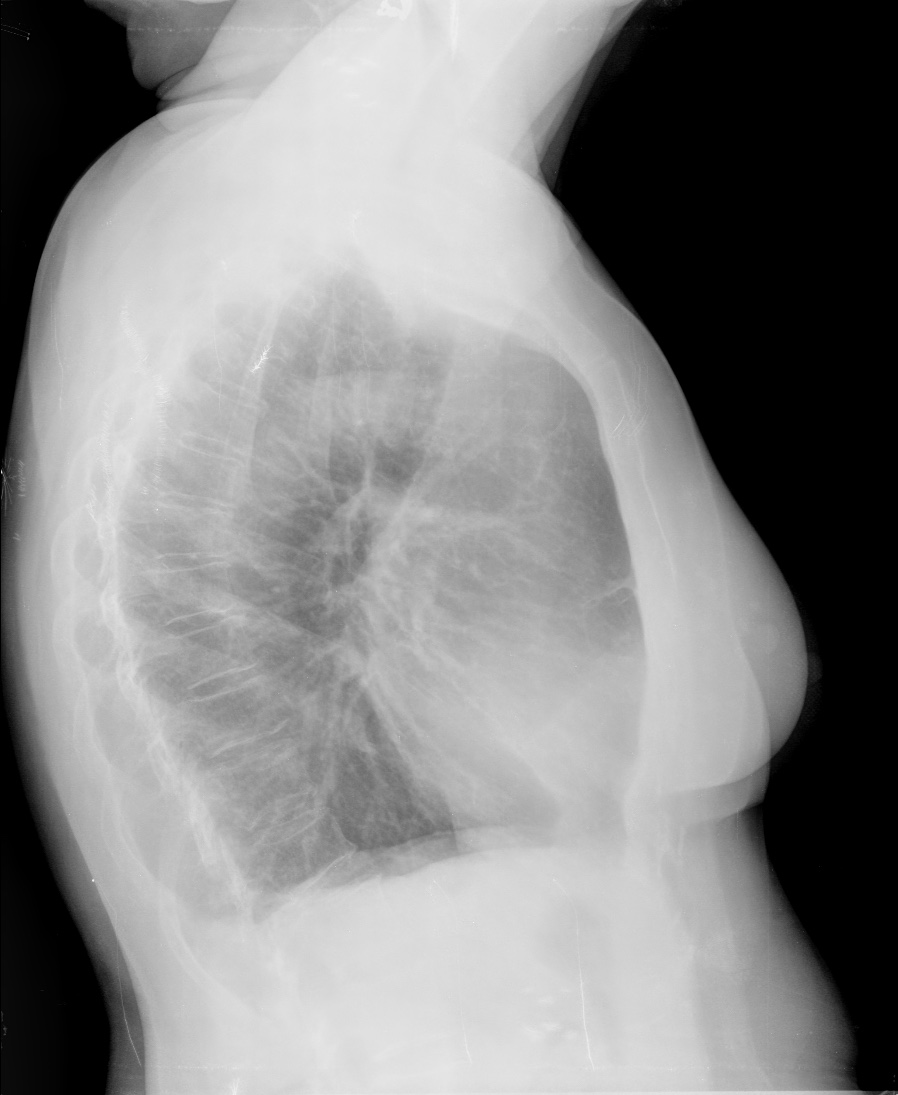

CASO: sospecha de neumonía.

Hallazgos:

- En un principio podríamos decir que existe un aumento de densidad retrocardiaco que podría ser compatible con condensación neumónica a dicho nivel, sin embargo estamos ante una placa poco inspirada, lo cual puede llevarnos a cometer errores diagnósticos.

- Se recomendó volver a realizar la radiografía, observar a continuación:

Ya no se observa el aumento de densidad retrocardiaco, la placa es normal.

INSPIRACIÓN: Una placa bien inspirada es aquella en la que se observar 6-7 arcos costales anteriores o 10-11 arcos costales posteriores. Lo contrario puede producir imágenes falsas de condensaciones o de seudocardiomegalia.